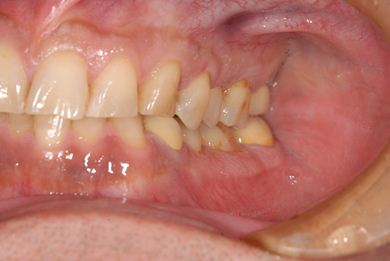

インプラント治療+セラミック治療+歯肉歯槽骨整形術

| 性別/年齢 | 男性 / 47歳 | ||||||||||||||||||||||||||||||||

| 主訴 | 悪いところの治療と、歯をきれいにしたい。 | ||||||||||||||||||||||||||||||||

| 治療方針 | 右下奥、保存不能な歯を抜歯し、インプラント治療にて、機能的・審美的回復を行う。 | ||||||||||||||||||||||||||||||||

| 治療内容 | インプラント2本、メタルボンドセラミッククラウン9本(メタルボンド用土台6本)、ハイブリッドセラミッククラウン2本(セラミック用土台2本)、ハイブリッドセラミックインレー5本、歯肉歯槽骨整形術 | ||||||||||||||||||||||||||||||||

| 治療期間 | 2年9ヶ月 |